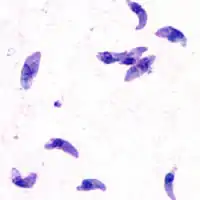

Toxoplasma gondii

O Toxoplasma gondii é um protozoário parasita intracelular obrigatório do grupo dos Apicomplexa, como outros parasitas como o Plasmodium. Há pouca variação entre os toxoplasmas presentes em diferentes partes do globo, podendo-se dizer que há, basicamente, três estirpes. A estirpe 1 é altamente virulenta e responsável pelos casos de encefalite grave em imunodeprimidos e passagem transplacentária. As estirpes 2 e 3 são avirulentas. O ciclo do toxoplasma é bastante flexível, posto que todas as suas formas são infectantes. Assim, ele pode reproduzir-se se as formas excretadas nas fezes dos gatos forem ingeridas por mamíferos ou outros felídeos por contaminação de água e alimentos, por exemplo, e também infectar o homem pelo mesmo modo, que, por sua vez, também pode infectar-se pela ingestão da carne de mamíferos contendo cistos com bradizoítas. Somente os gatos liberam estruturas infectantes nas fezes.